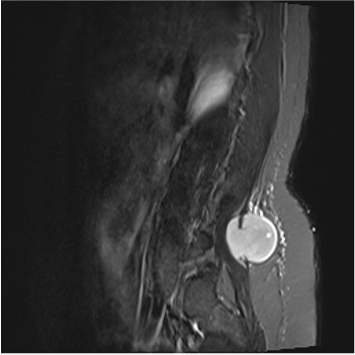

Monophasic Paravertebral Lumbar Synovial Sarcoma in an Adult Patient: Case Report

Bruno Amaral Santos, Beatriz Segatto de Oliveira, Paulo Eduardo Hernandes Antunes, João Guilherme Carvalho de Oliveira Santos, Eloy Theodoro José do Prado, Felipe Hammoud de Menezes, Ellen Diniz de Menezes

bjcr131